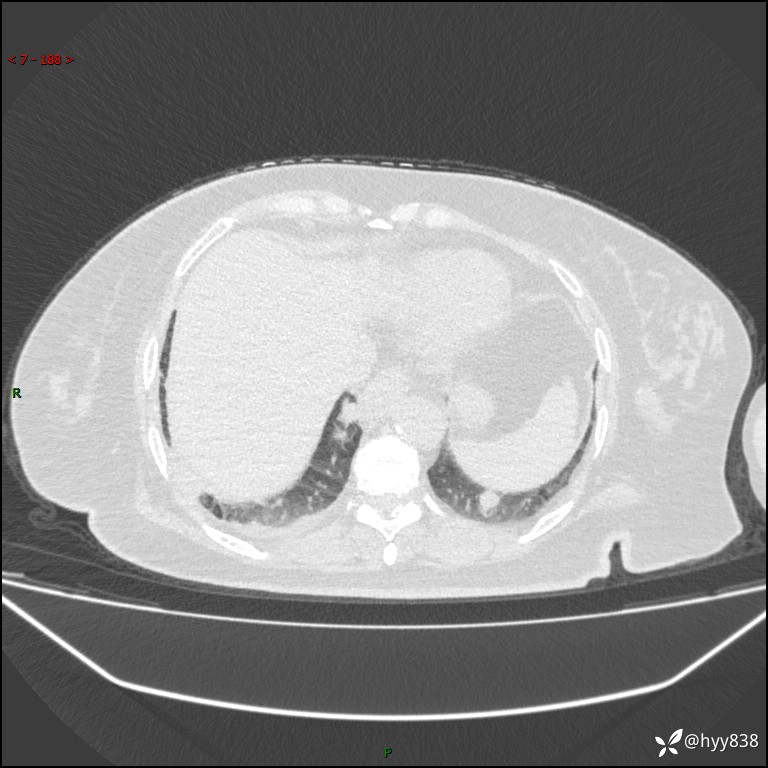

患者性别:女

患者年龄:57岁

简要病史:昏迷入院

临床诊断:昏迷

胸部 CT平扫、